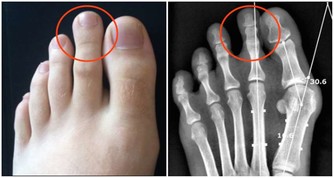

Q1:高尿酸是怎麼來的?

人體尿酸有兩種來源:一是內源性的,是有身體內的氨基酸、核酸等分解而代謝出來,約佔80%;二是外源性的,是有吃的食物中的核苷酸分解代謝而出,佔20%左右。

如果是原發性的高尿酸血症,採用低嘌呤的飲食,雖然可以降低尿酸水平,但是因為身體內已經含有大量的尿酸鹽沉積在關節腔內,必須用藥無治療才能降低尿酸的水平,